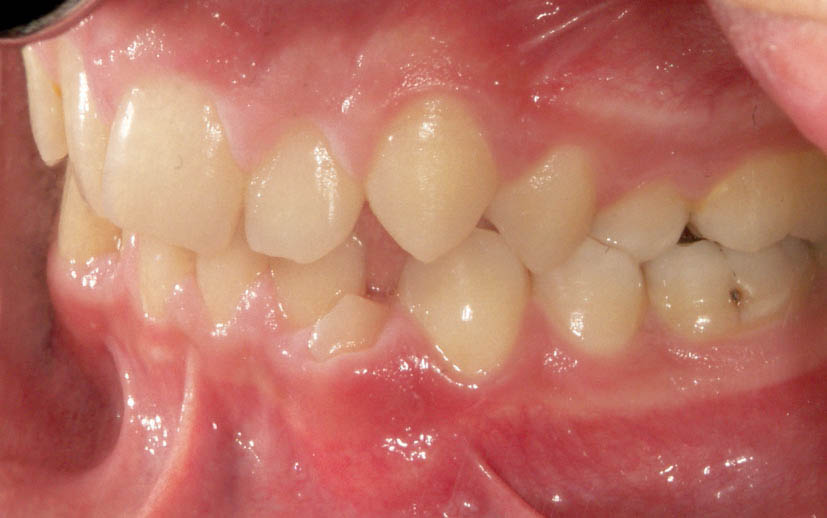

شکل 104-2: اکلوژن کلاسI در سمت چپ